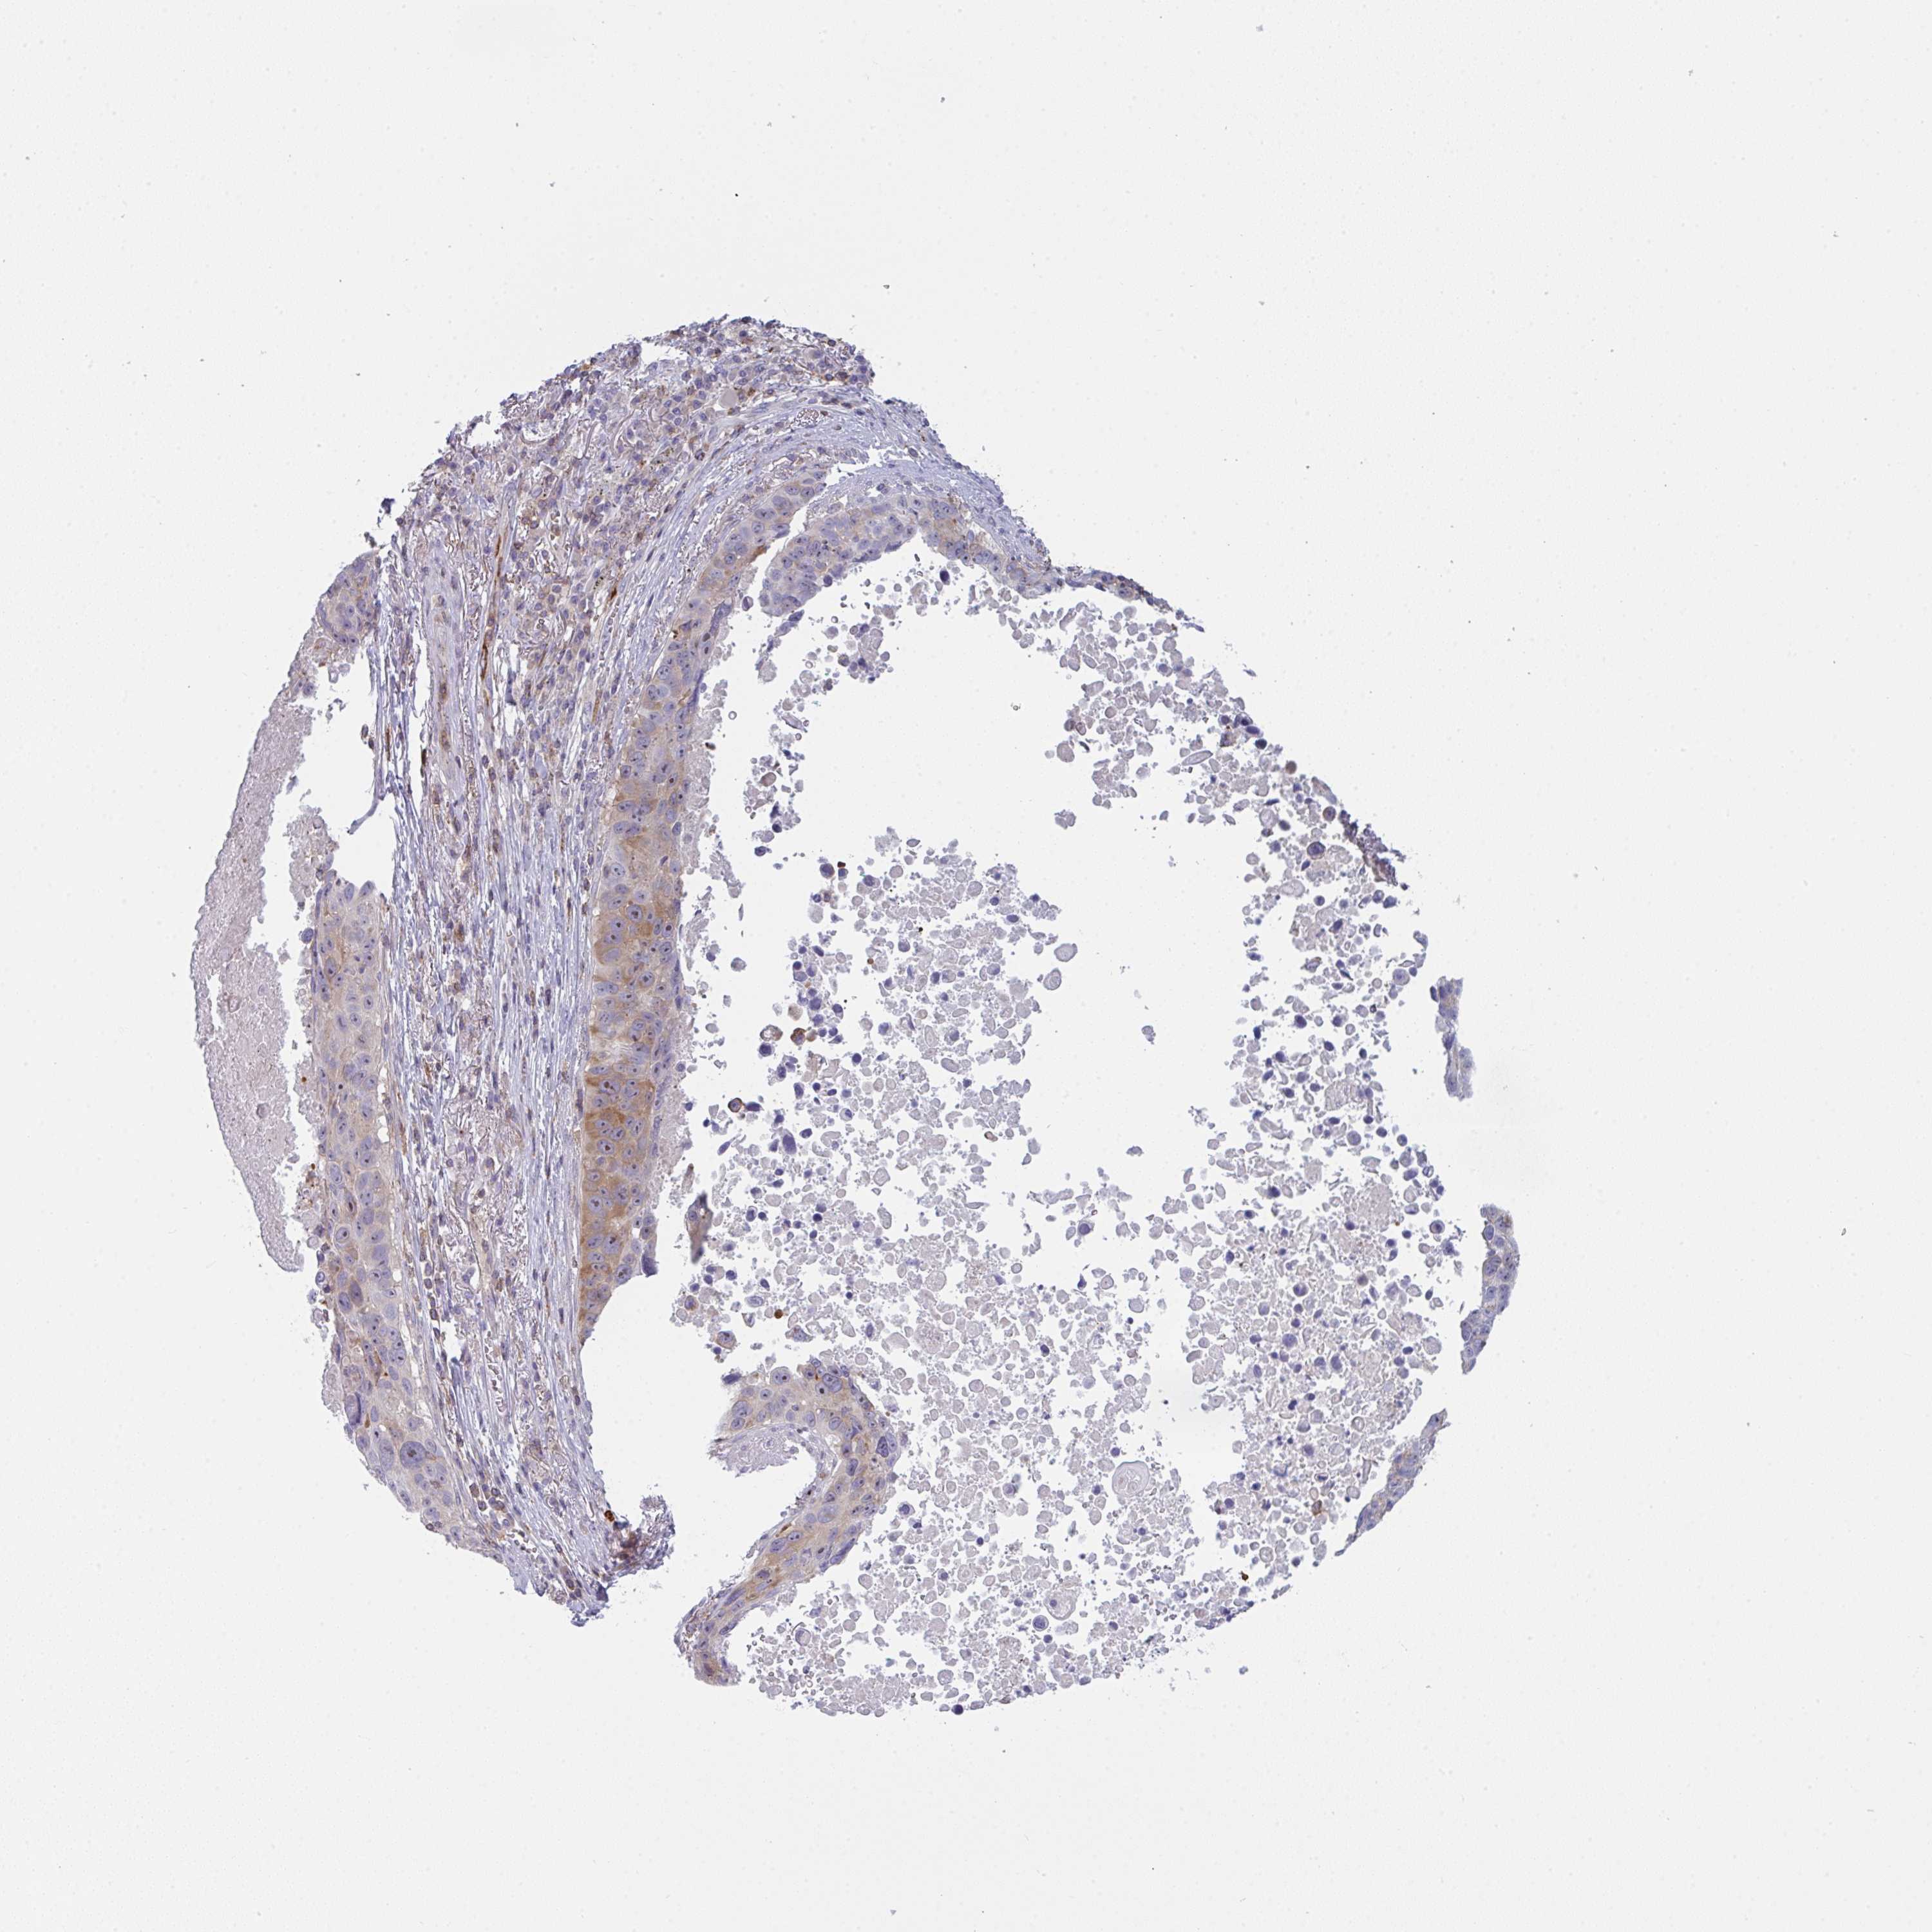

LUNG ADENOCARCINOMA (VALIDATION) - Interactive survival scatter ploti

The Survival Scatter plot shows the clinical status (i.e. dead or alive) for all individuals in the patient cohort, based on the same data that underlies the corresponding Kaplan-Meier plots. Patients that are alive at last time for follow-up are shown in blue and patients who have died during the study are shown in red.

The x-axis shows the expression levels (FPKM) of the investigated gene in the tumor tissue at the time of diagnosis. The y-axis shows the follow-up time after diagnosis (years). Both axes are complimented with kernel density curves demonstrating the data density over the axes. The top density plot shows the expression levels (FPKM) distribution among dead (red) and alive patients (blue). The right density plot shows the data density of the survived years of dead patients with high and low expression levels respectively, stratified using the cutoff indicated by the vertical dashed line through the Survival Scatter plot. This cutoff is automatically defined based on the FPKM cutoff that minimizes the p-score. The cutoff can be changed by dragging the vertical line or by entering a cutoff value in the square labeled "Current cut-off".

Under the Survival Scatter plot the p-score landscape (black curve; left axis) is shown together with dead median separation (red curve; right axis). Dead median separation is the difference in median mRNA expression between patients who have died with high and low expression, respectively. It is calculated as follows: median FPKM expression of dead patients with high expression - median FPKM expression of dead patients with low expression. This is intended to aid the user in visually exploring custom cutoffs and the associated p-scores and dead median separation.

Individual patient data is displayed and can be filtered by clicking on one or more of the category buttons on the top of the page. Categories describing expression level and patient information include: high, low, alive, dead, female, male and tumor stages. The scale of the x-axis can be toggled between linear and log-scale by clicking on the "x log" button. Mouse-over function shows TCGA ID, patient information and mRNA expression (FPKM) for each patient.

& Survival analysisi

Kaplan-Meier plots summarize results from analysis of correlation between mRNA expression level and patient survival. Patients were divided based on level of expression into one of the two groups "low" (under cut off) or "high" (over cut off). X-axis shows time for survival (years) and y-axis shows the probability of survival, where 1.0 corresponds to 100 percent.

CD80 is not prognostic in Lung Adenocarcinoma (validation)

: 3.56

Average pTPM 5.3

Number of samples 105